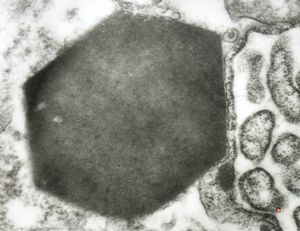

M,62y. | crystalline inclusion in endoplasmic reticulum - bone marrow, plasmocytoma

M,62y. | crystalline inclusion in endoplasmic reticulum - bone marrow, plasmocytoma

M, | crystalline inclusions in plasmocyte

M, | crystalline inclusions in plasmocyte

M,15y. | crystalline inclusion in plasmocyte - histiocyto-eosinophilic granuloma

M,59y. | crystalline inclusions in plasmocyte - plasmocytoma